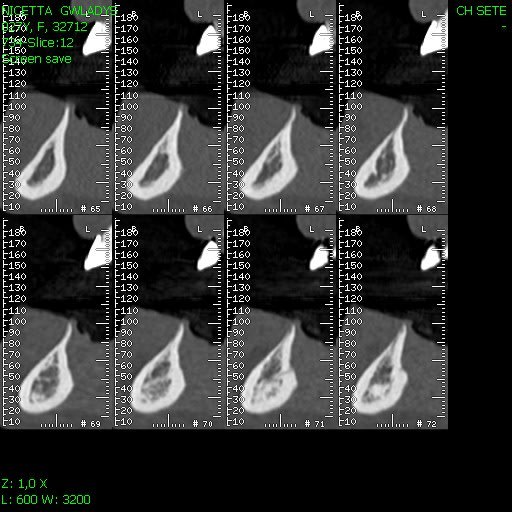

la patiente a 27 ans, elle aperdu ces 4 incisives mandibulaires il ya plusieurs années dans un accident.

La crête osseuse est ultra résorbée et très fine.

mon idée c'est que c'est possible, et vous vous le feriez? et quelle prothèse?

çà va faire des implants de 10-11.5 mm avec une partie prothétique de 22-23 mm de haut! pourquoi pas alors 3 implants (32-42 et un médian pour soutenir toute cette structure qui va reconstituer à la fois dents mais aussi partie de crête résorbée)